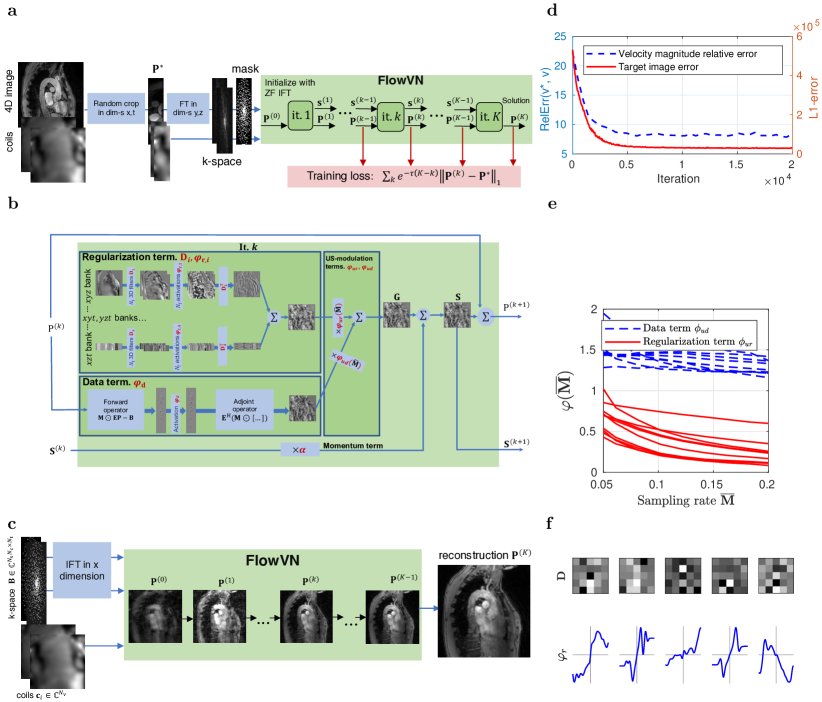

4D flow MRI reconstruction with FlowVN

The FlowVN architecture improves HamVN in the following ways: (i) linear activations are used instead of radial basis functions (RBF), (ii) the network is conditioned on the sampling rate, (iii) exponential weighting of intermediate layers is used as regularization, (iv) real and imaginary parts of the signal are filtered by shared weights, (v) momentum is considered during gradient descent (GD) unrolling, and, (vi) the data term allows tunable activation functions. The network is trained for a wide range of acceleration factors by allowing acceleration dependent weighting of data consistency and filtering steps.

A deep variational network can be seen as a differentiable sequence of an unrolled numerical optimization scheme. To enable learning, such sequence is then relaxed by allowing tunable filter weights and activation functions. As described in Methods, we unroll = steps of a gradient descent with momentum governed by a scalar :

At each -th layer the current complex-valued spatio-temporal image estimate is represented, while maintains a running average of update steps. The update step consists of the data consistency and regularization terms (see Methods and Supplementary Algorithm 1 for details), that are weighted according to the sampling rate ( is the acceleration factor) via tunable activation functions and , respectively. The data consistency term modulates the k-space data residual via an activation function and maps them back to the image space via a conjugate imaging operator. The regularization term at each layer contains 3D filters grouped into 4 banks, where each bank performs convolutions in 3 dedicated dimensions, namely , , and , therefore avoiding costly 4D convolutions. To avoid overfitting, we assume shared filters and activation functions that operate on real and imaginary components of the image. Note that both data and regularization terms do not assume correlations between real and imaginary parts of the signal, as highlighted in Fig. 2b.

The image estimate of the final layer can be then seen as a function of the k-space samples and network parameters . To tune the network parameters we minimize the layer-wise exponentially weighted image reconstruction loss:

over the retrospectively undersampled training dataset , where is the ground truth image. Layer weighting is controlled by parameter : when , the reconstruction error is penalized equally across layers, therefore gradients of network parameters have lower variance during stochastic optimization, yielding faster convergence. On the contrary, when , only reconstruction at the final layer is minimized, which improves fitting accuracy on the training data. It is worth mentioning that controls the trade-off between training reconstruction residual and network regularity. Similarly to Landweber iterations 26, 15 and deep supervision 27, such implicit regularization penalizes irregular representations at intermediate layers and favors networks that can provide fast reconstruction. We propose to initialize with zero and then gradually increase it according to the training schedule (see Methods).

To demonstrate the validity of our approach, we note that the extracted velocity magnitude error in the aorta decreases simultaneously with the target reconstruction error during training, as shown in Fig. 2d, therefore indicating that the target image error is a valid training surrogate. It can be seen from Fig. 2e that the regularization term is suppressed for lower acceleration factors (higher sampling rate ). A subset of learned FlowVN parameters is shown in Fig. 2f illustrating that learned convolutions perform direction-dependent filtering.

In this work we have further developed the VN architecture 15, 36, 37 to accommodate high performance undersampled 4D flow reconstruction with limited training. Namely, we avoid exponential model complexity growth by avoiding 4D convolutions and by using separable 3D convolutions that are shared for real and imaginary parts of the image. Furthermore, in contrast to the original HamVN 15, we train our FlowVN for a wide range of undersampling factors by allowing the regularization term to depend on them. As illustrated in Fig. 2e, regularization scaled by decreases as more samples are available, while the data term stays constant for most of the layers. Such conditioning allows network training on a larger variety of artefacts and as it is necessary in practice, since for a given fixed acquisition time, the precise value of the undersampling factor is not known a priori and depends on breathing and cardiac motion patterns. We hypothesize that the wide range of acceleration factors which were used simultaneously to train the FlowVN provided a diverse collection of aliasing artefacts and enabled robust learning on a remarkably limited training set of 11 subjects. The exponential weighting of the layer-wise reconstruction loss (3) further regularized FlowVN parameters by penalizing the nonlinear behaviour presented in HamVN reconstructions. Supplemental Fig. 6 and Table 3 provide quantification of reconstruction accuracy effects attributed to the modifications proposed with FlowVN. In particular, modifications to the network architecture result in a model that can better adapt to data and yield higher accuracy for retrospectively undersampled experiments, while the proposed exponential weighting of the training loss improves accuracy of the prospective evaluation, which indicates better generalization ability. It is worth noting, that FlowVN has only 1% more tunable parameters compared to HamVN (c.f. Table 1), while improving reconstruction nRMSE by 23% (averaged over acceleration factors as given in Supplemental Fig. 6). We note that 4D flow MRI greatly benefits from using coil information during reconstruction (see Supplementary Table 3). Accordingly, comparison with single-coil reconstruction networks 18 has limited benefit.

To enable backpropagation to be carried out with limited GPU memory, we employ spatio-temporal equivariance of the convolution and exploit the fact that k-space is fully sampled in the readout dimension for Cartesian acquisitions. Therefore, to draw a training sample, we perform random cropping of width and in dimensions and respectively and simulate Fourier encoding in dimensions as illustrated in Fig. 2(a). The network was implemented using the Tensorflow framework 32. Fully-sampled and partial Fourier acquisition data from 11 healthy volunteers was used during training.